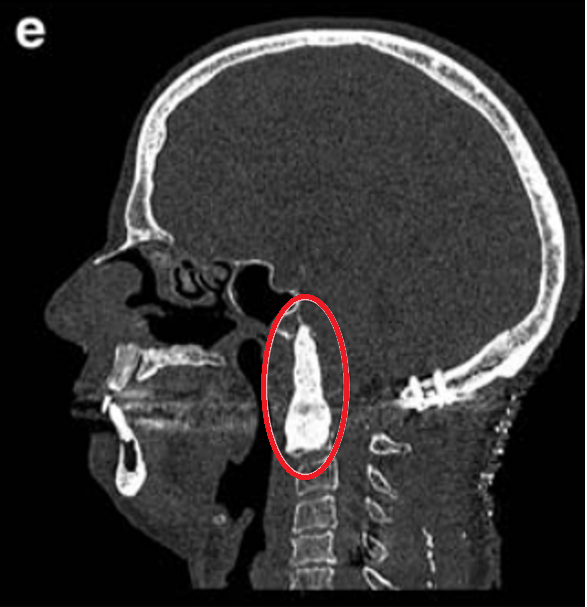

▼图e:术后用骨水泥填充术腔,从中斜坡至C2椎体水平。术后10天行枕-颈固定术。